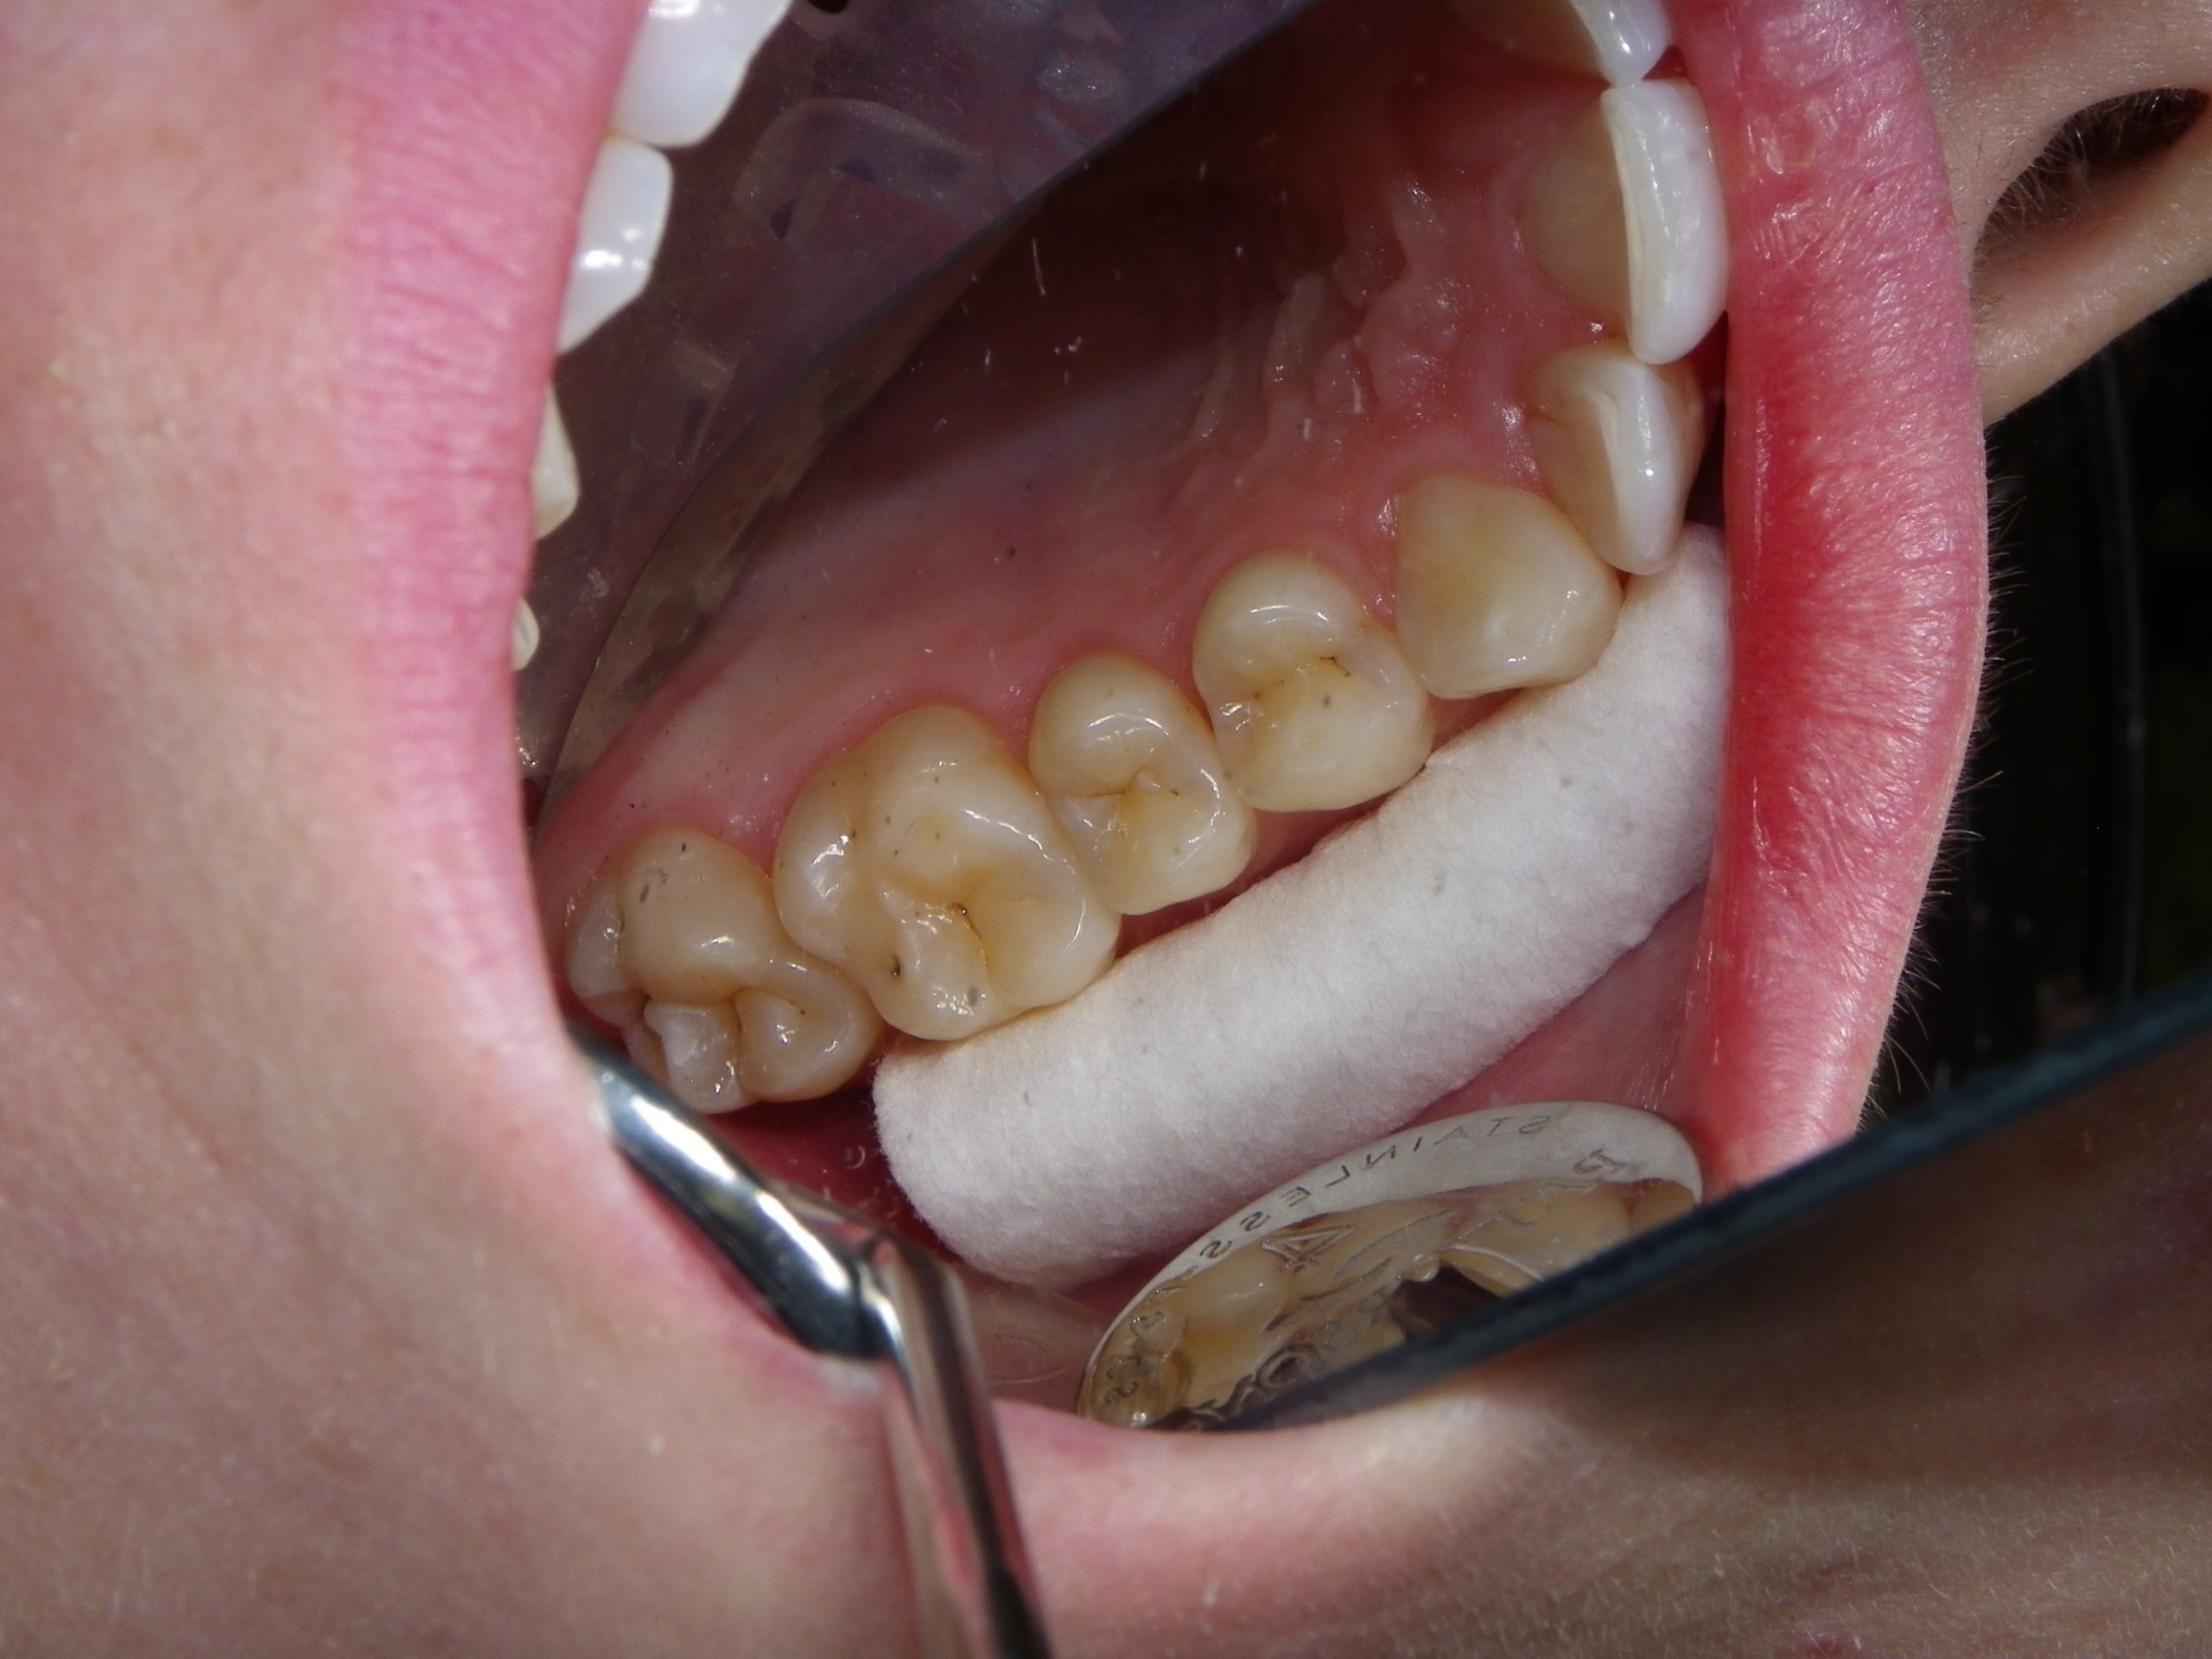

After educating the patient on the decay risks of this behaviour, oral hygiene instruction and a recommendation for a daily fluoride rinse, she can now take action to prevent any new cavities from developing for the rest of her life. There were many areas of decay between other teeth that we elected not to fill due to their small size, and hopefully they remain arrested / remineralized! (Aluminum oxide Air abrasion via PrepStart, 32% Phosphoric acid etch with Benzalkonium Chloride and AllBond Universal adhesive from Curion, Esthet-X Flowable A2 liner from Dentsply, Simplishade Medium resin core from Kerr).